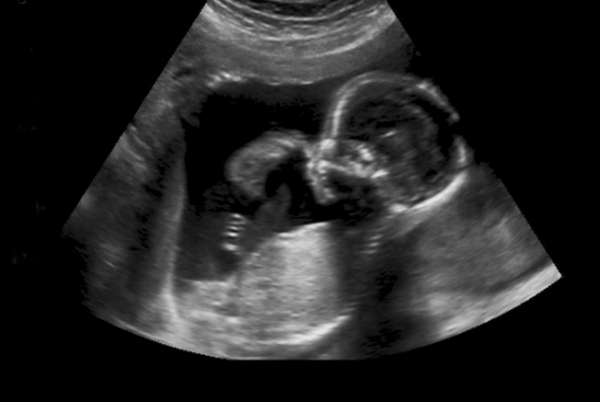

A newborn baby symbolises vulnerability and wonder in this world—a representation of creation in its most pure and fragile state. How we welcome the new into this world reflects much of how we treat the most vulnerable in our world.

For many, the welcoming of a child into the world is filled with expectancy and joy, albeit the unknown. However, for many refugee and migrant women in South Africa, bringing life into this world means confronting debt, fear and uncertainty. Giving birth in South Africa’s public health system for refugee and migrant women has become increasingly extracting. Free healthcare services are guaranteed in

the Constitution to all pregnant and lactating women and children under the age of six. However, since 2020 Jesuit Refugee Service (JRS) became aware of public hospitals in Gauteng, requesting mothers who are not South African to pay for ante-natal and maternal health care services. JRS has had reports of mothers being told to pay between R250-R400 for their ante-natal check-ups. The cost of natural delivery has ranged between R5000-R8000 and up to R25000 for a Caesarian-section. A price which

for most in South Africa is inconceivable.